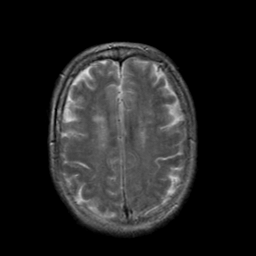

Stroke:T2-weighted MR #2 -- Slice #18

[Home][Help][Clinical] Slice 18